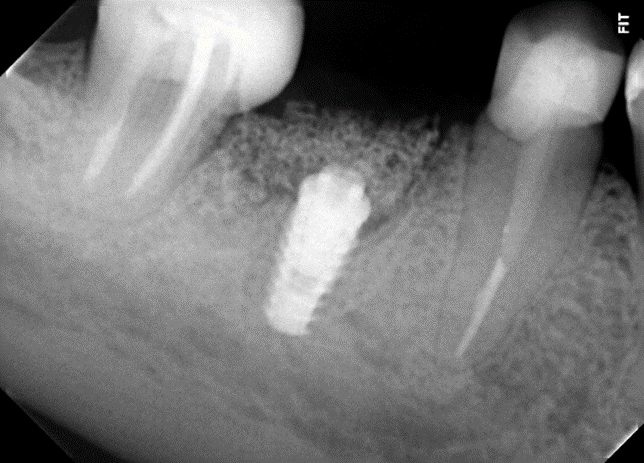

Uma paciente de 62 anos de idade apresentou-se com queixa de odor ruim na região do dente 46, pus, bolsa profunda e sangramento à sondagem. Os exames radiográficos evidenciaram lesão periapical, tratamento endodôntico e uma linha de fratura condenando a sobrevivência do elemento dentário 46. Assim, o elemento foi extraído e foi instalado um implante dentário de conexão interna morse no momento da exodontia. O mesmo foi estabilizado a 20Ncm e o parafuso de cobertura foi instalado. Em seguida, um biomaterial de origem bovina foi compactado no GAP e uma membrana não absorvível foi posicionada protegendo o biomaterial.

Após a análise clínica e tomográfica foi realizado o planejamento do caso: exodontia do dente 46 com a instalação imediata de um implante Cone Morse de corpo cônico (Maestro 4.0 X 9 – Implacil De Bortoli, São Paulo, Brasil), regeneração óssea guiada com biomaterial de origem bovina e colocação de uma barreira regenerativa não absorvível Cytoplast.